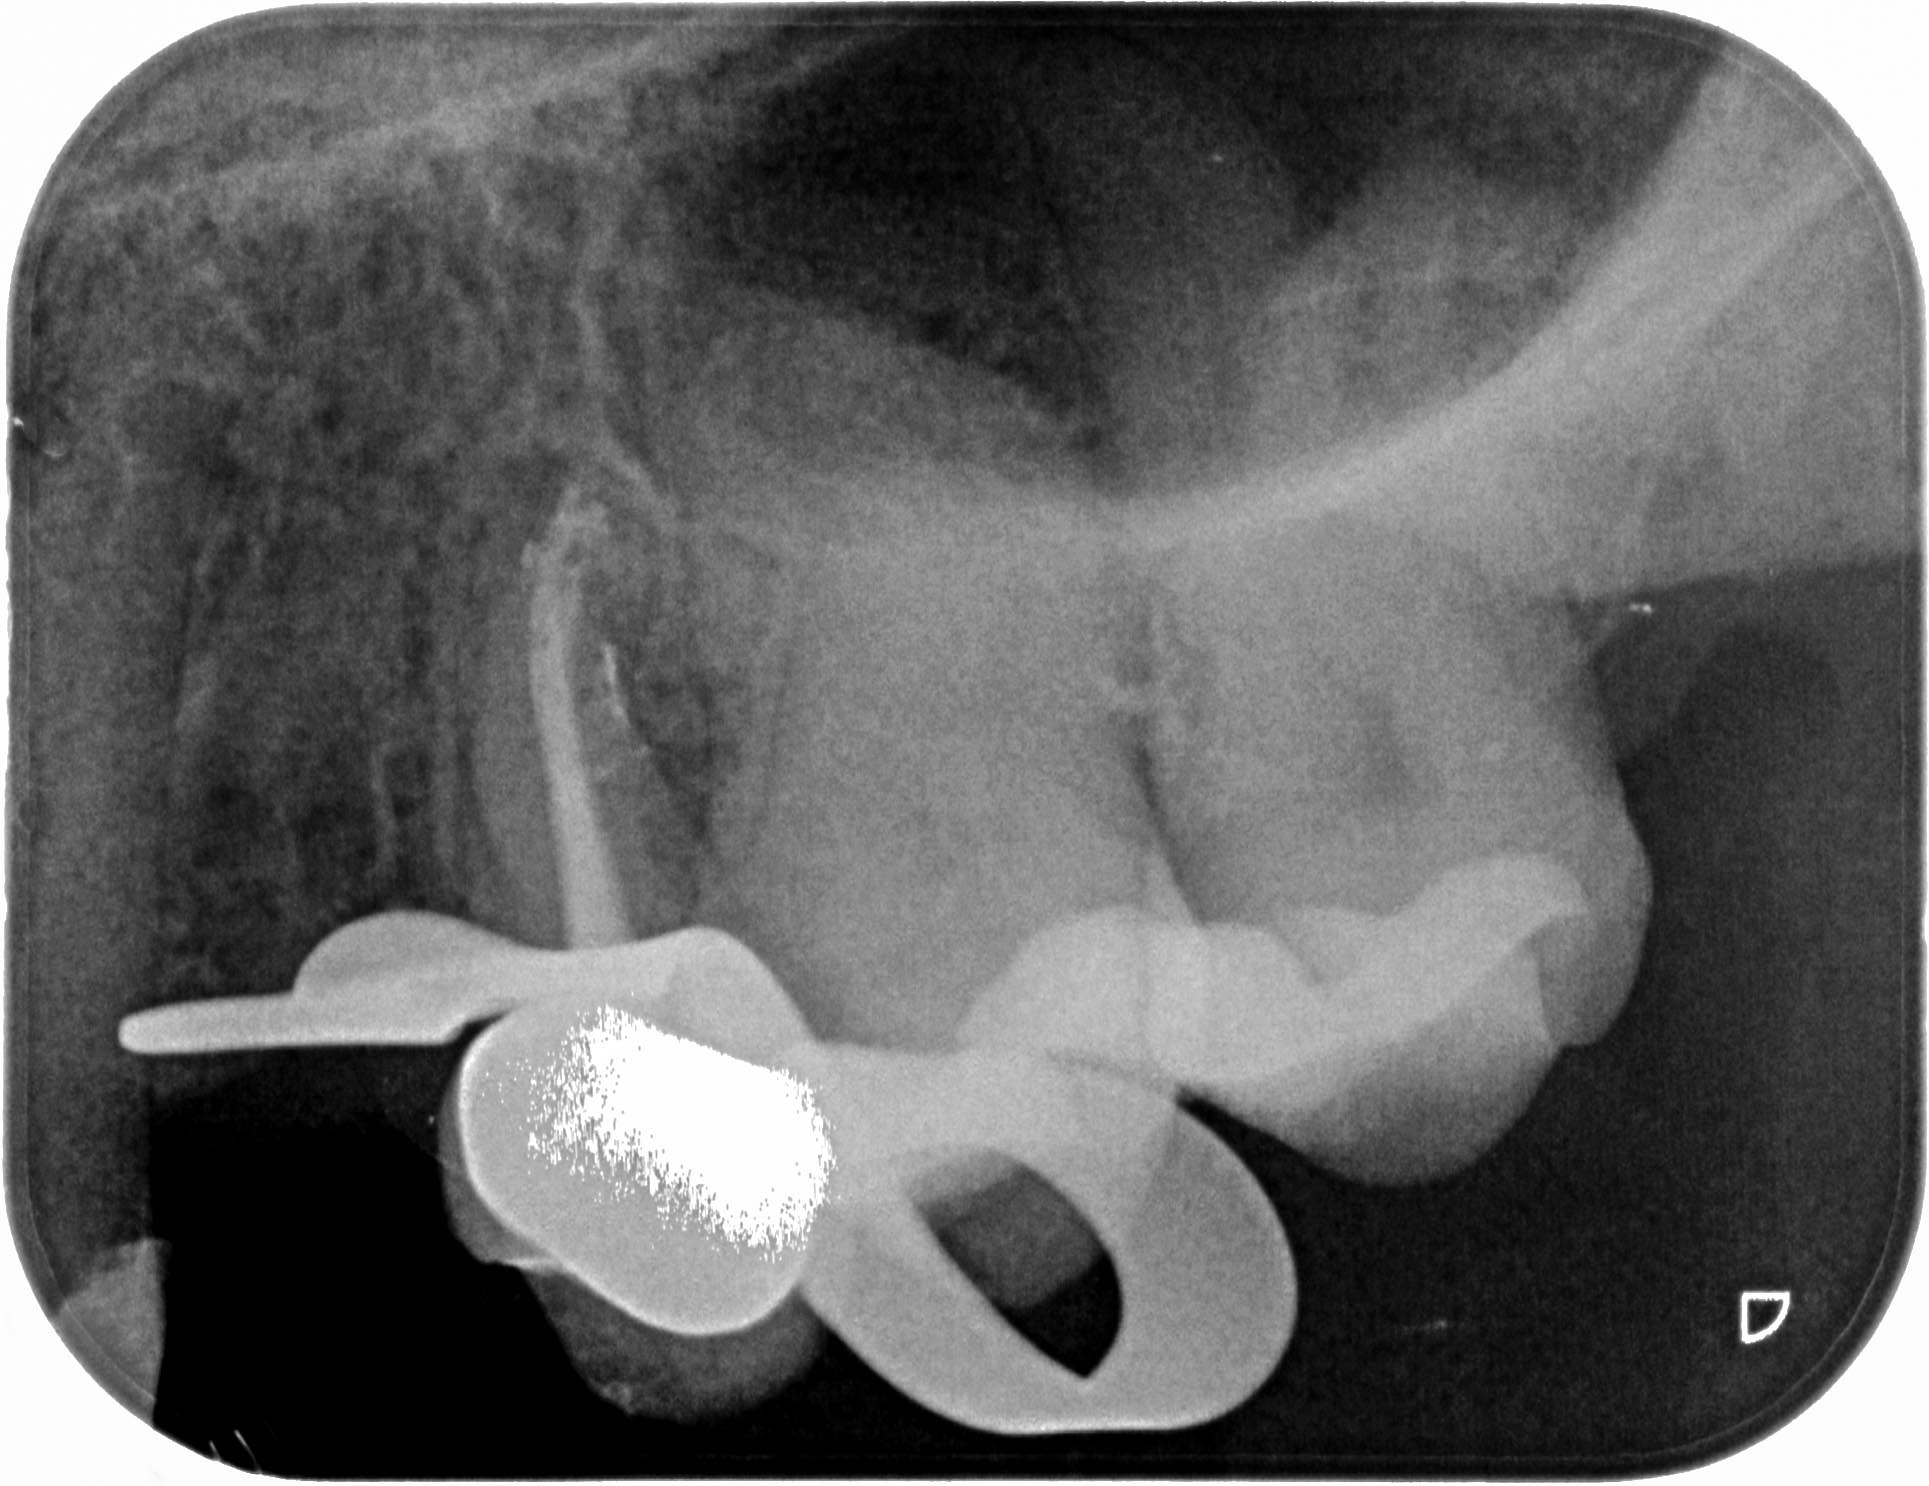

KM_25-1 Veröffentlicht 16. November 2015 am 1929 × 1486 in 5 Prämolaren (2) Zahn 25 post WF, exzentrische Aufnahme